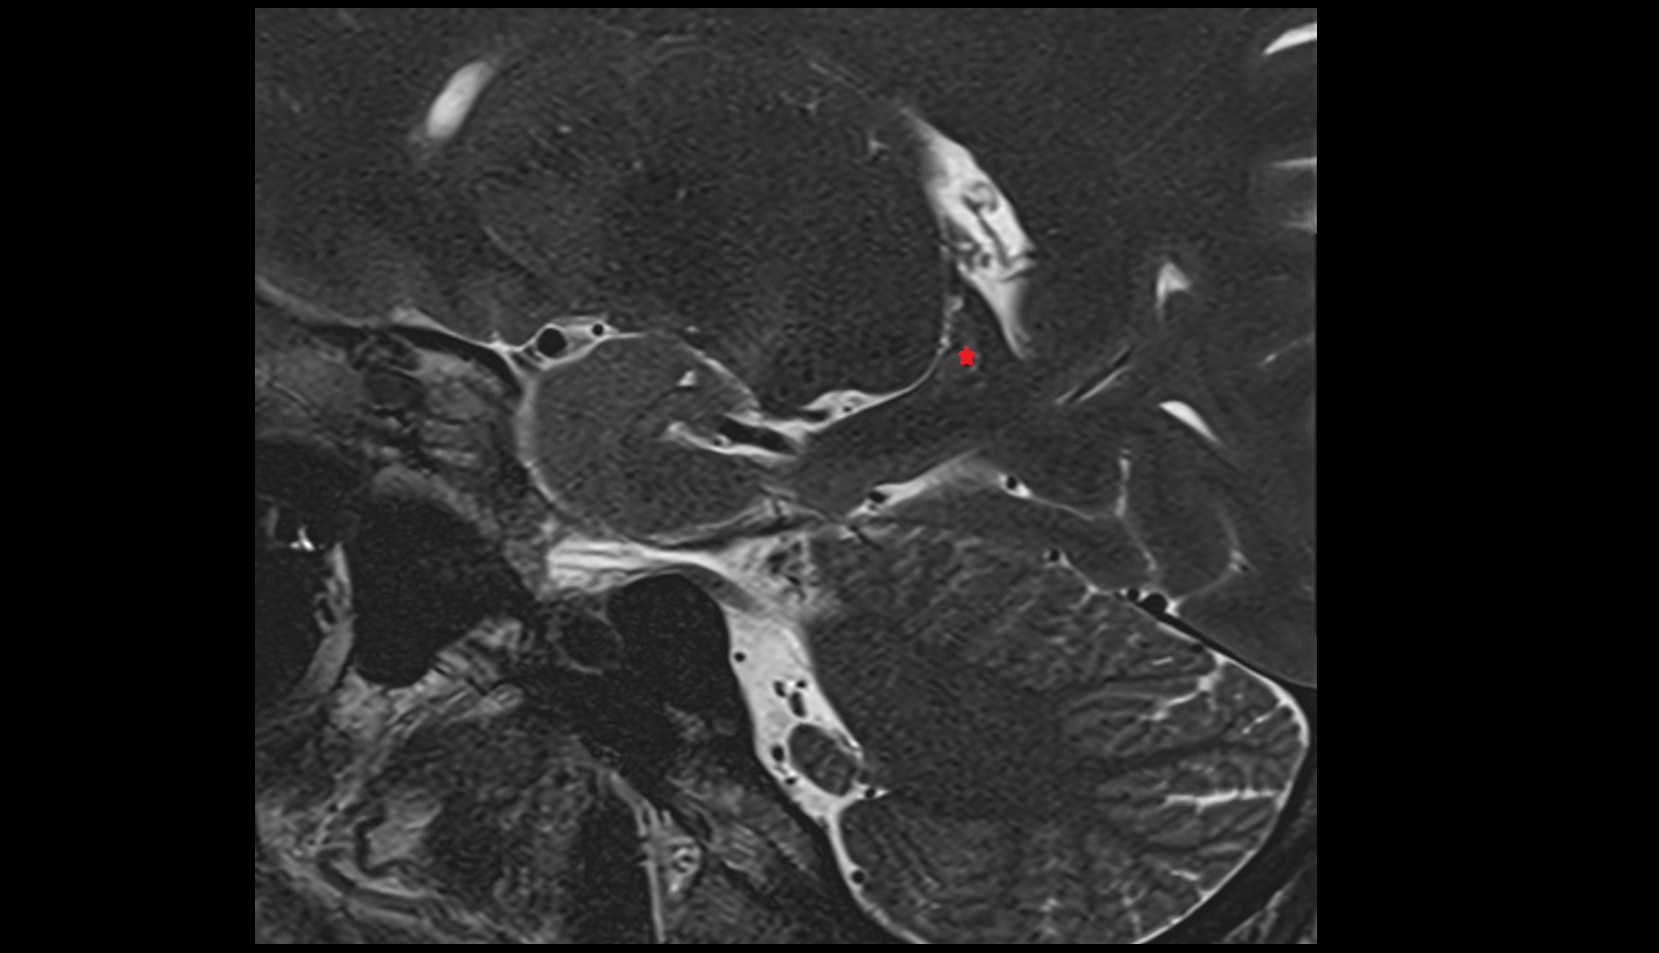

- Temporomandibular joint

- Mandibular condyle

- Mandibular fossa

- Articular disc of temporomandibular joint

- Articular eminence